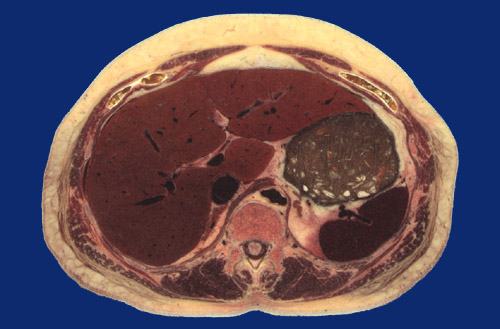

Identify the following regions in the image above: Rectus abdominus - External oblique - Serratus posterior inferior - Latissimus dorsi - Sacrospinalis - Multifidus - Right lobe of liver - Left lobe of liver - Body of stomach - Spleen - Diaphragm - Descending aorta - Inferior vena cava - Left adrenal gland - Right adrenal gland - Vertebral body - Spinal cord